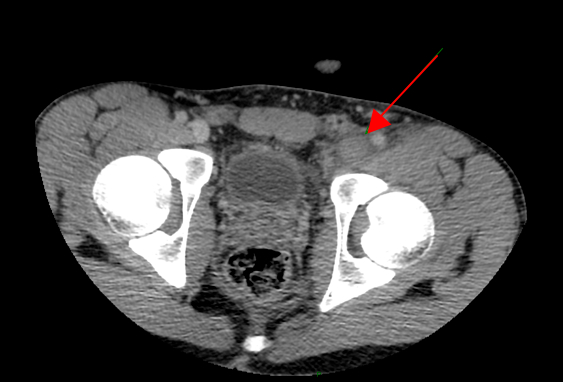

Per la storia di dolore inguino-scrotale e la difficoltà a deambulare viene eseguita una ecografia scrotale con riscontro collaterale di trombosi completa dell’asse popliteo iliaco femorale di sinistra! Per valutare l’estensione della trombosi viene eseguita angio-TC toraco-addominale che evidenzia la presenza di una parziale trombosi del tratto sottorenale della vena cava inferiore con trombosi completa di entrambe le vene iliache comuni, della vena iliaca esterna di sinistra e della femorale comune omolaterale associata inoltre a trombosi parziale della vena iliaca interna di destra (Figure 4 e 5).